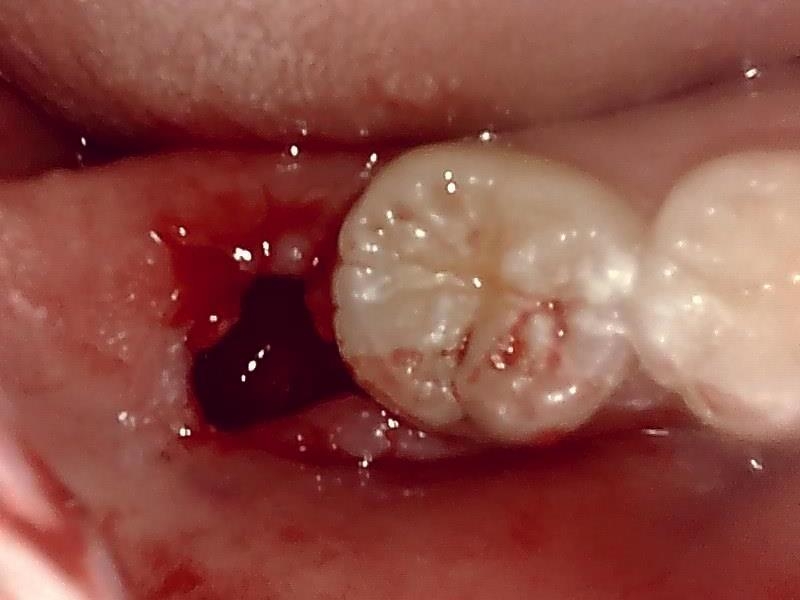

抜歯窩

縫合

右上8番智歯

抜去歯

歯肉を切開し、歯が見えるようにして、

周辺の骨を削らないように親知らずを分割し抜きやすくしていきます。

この抜歯法により術後の腫れ痛みが大幅に軽減されます。

傷口は最小限に、骨は極力削らずに行います。

骨が歯を覆っているケース以外は骨を削ることはありません。

親知らずのみにアプローチし歯を分割し最小限の傷口で取り出します。